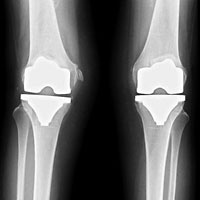

Abb. 1

Knieteilprothese

Knietotalprothese

Gelegentlich liegt die Arthrose nicht nur in einem der drei Teile des Kniegelenks, sondern gleichzeitig in mehreren Bereichen vor. Sind sowohl die Innen- als auch die Aussenseite befallen, wird eine Knietotalprothese eingesetzt. Sind hingegen die Innenseite und das Areal hinter der Kniescheibe befallen, kann eine Kombination von zwei Teilprothesen eingesetzt werden.